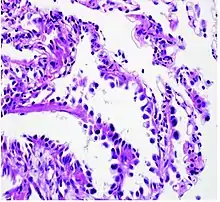

Histopathology of lepidic predominant adenocarcinoma.

• lepidic predominant [18]

Cell patterns identifying subtypes are associated with prognosis, ranging from favorable (lepidic) to intermediate (acinar and papillary) to poor (micropapillary and solid).[2]